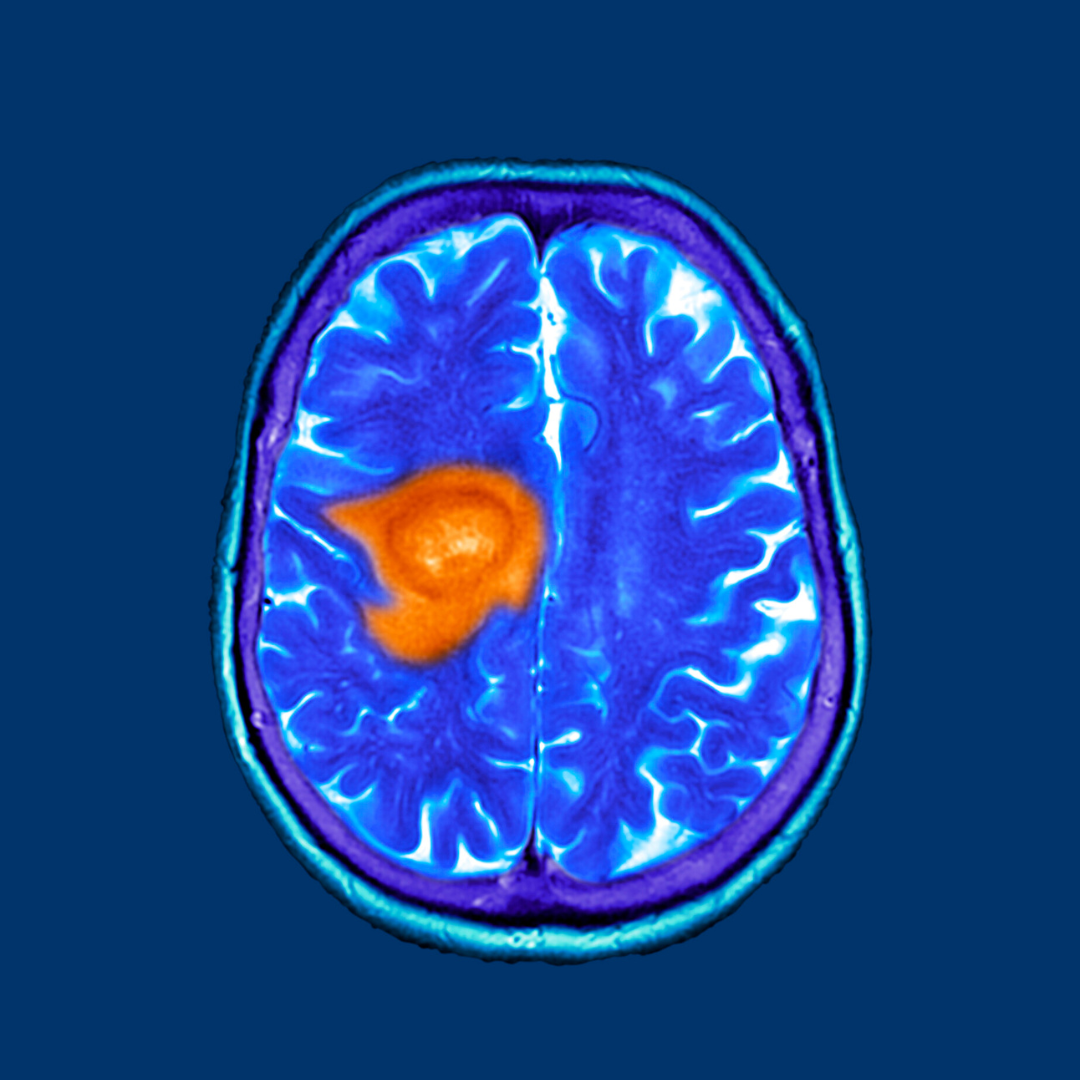

O glioblastoma, também conhecido como glioblastoma multiforme, é um tipo de câncer cerebral altamente agressivo e incurável.

O glioblastoma é uma neoplasia maligna que se origina a partir das células gliais do cérebro. Sua nomenclatura, “glioblastoma multiforme,” reflete sua capacidade de assumir várias formas e é caracterizada por sua rápida progressão. É o tipo mais comum de tumor cerebral primário em adultos, representando aproximadamente 15% dos casos.

O diagnóstico de glioblastoma é desafiador e requer uma série de exames clínicos e de imagem. A ressonância magnética (RM) é o exame de escolha para avaliar a localização e a extensão do tumor. A confirmação geralmente é feita por meio de uma biópsia cerebral.